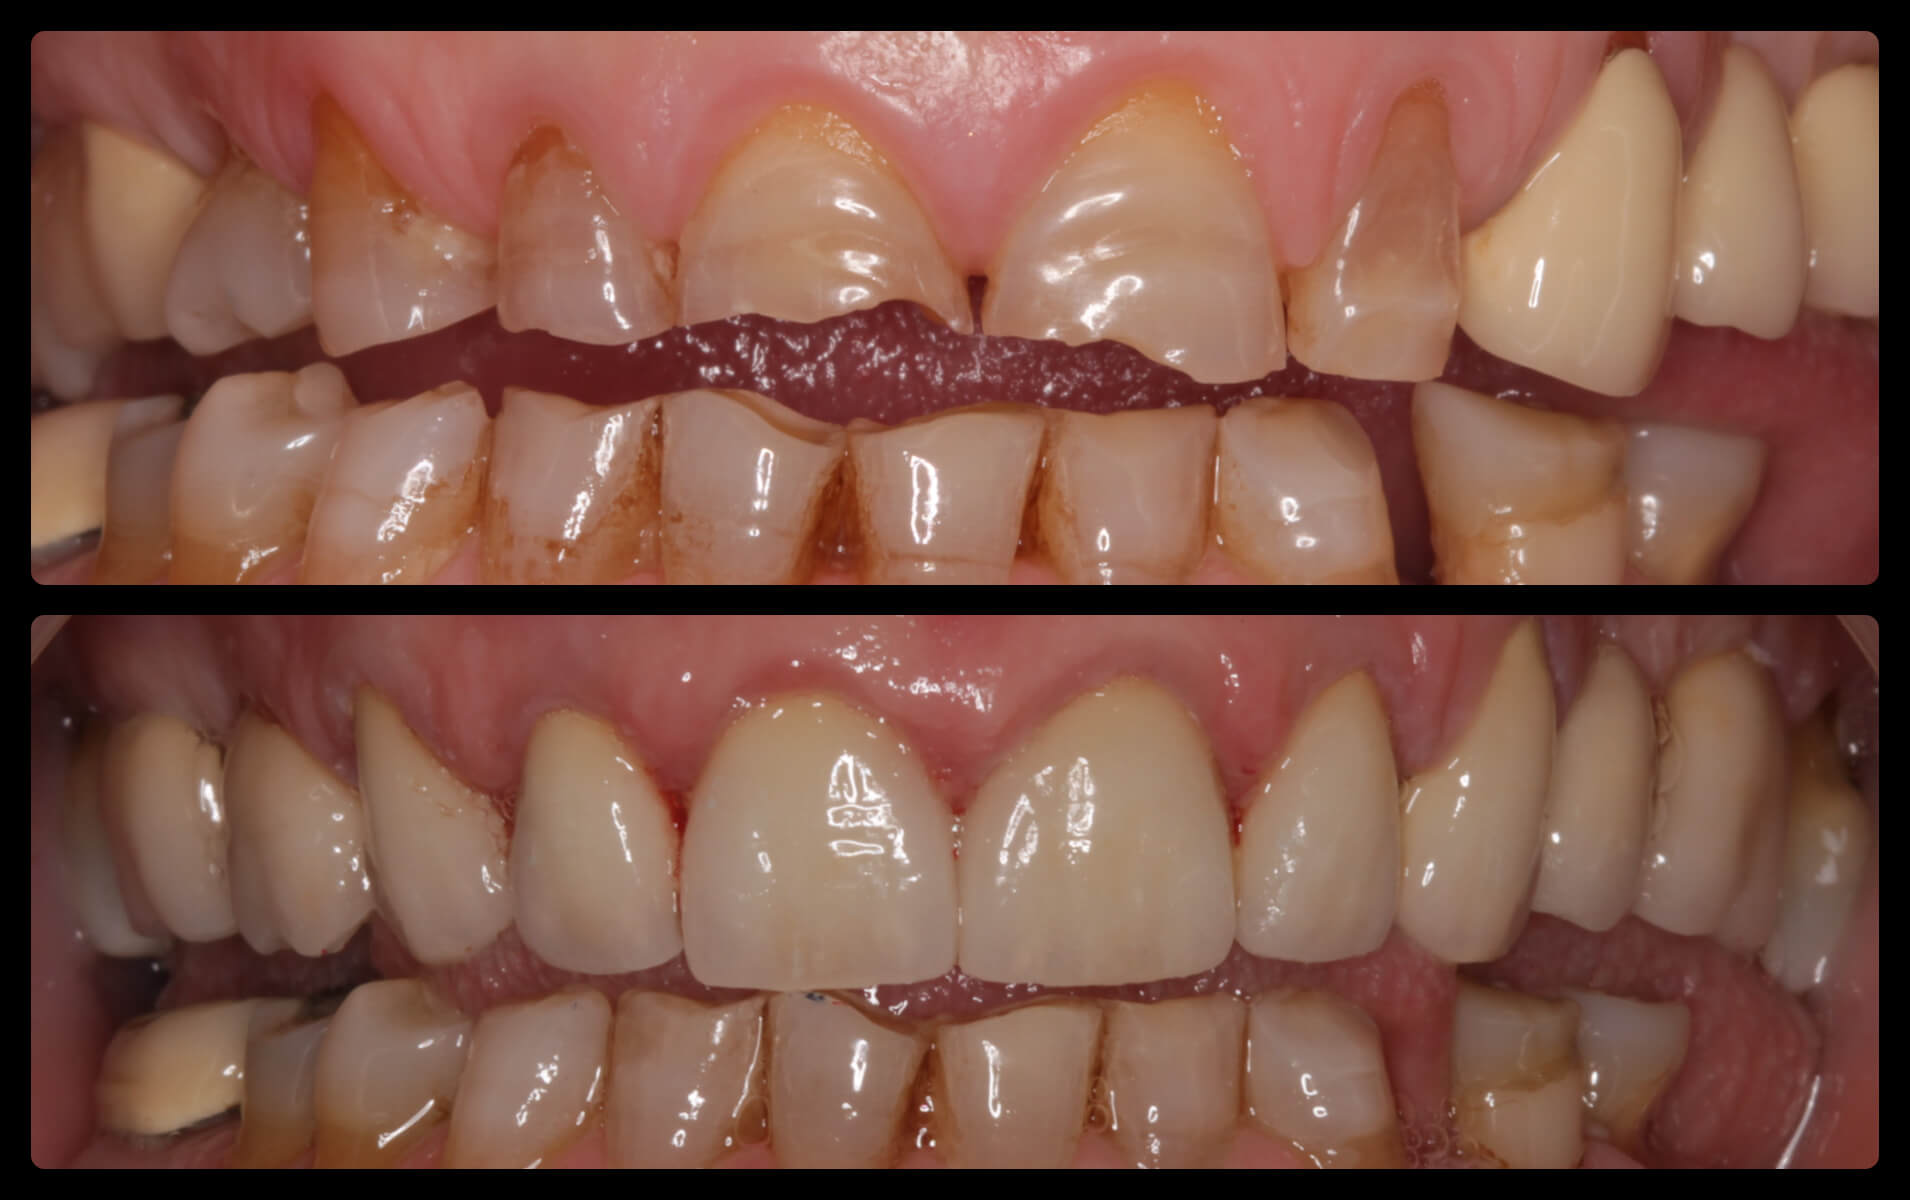

ΠΡΟΣΘΕΤΙΚΕΣ ΑΠΟΚΑΤΑΣΤΑΣΕΙΣ ΜΕ ΣΥΝΔΥΑΣΜΟ ΛΕΥΚΑΝΣΗΣ, ΣΥΝΘΕΤΩΝ ΡΗΤΙΝΩΝ ΚΑΙ ΟΛΟΚΕΡΑΜΙΚΩΝ ΟΨΕΩΝ ΚΑΙ ΣΤΕΦΑΝΩΝ